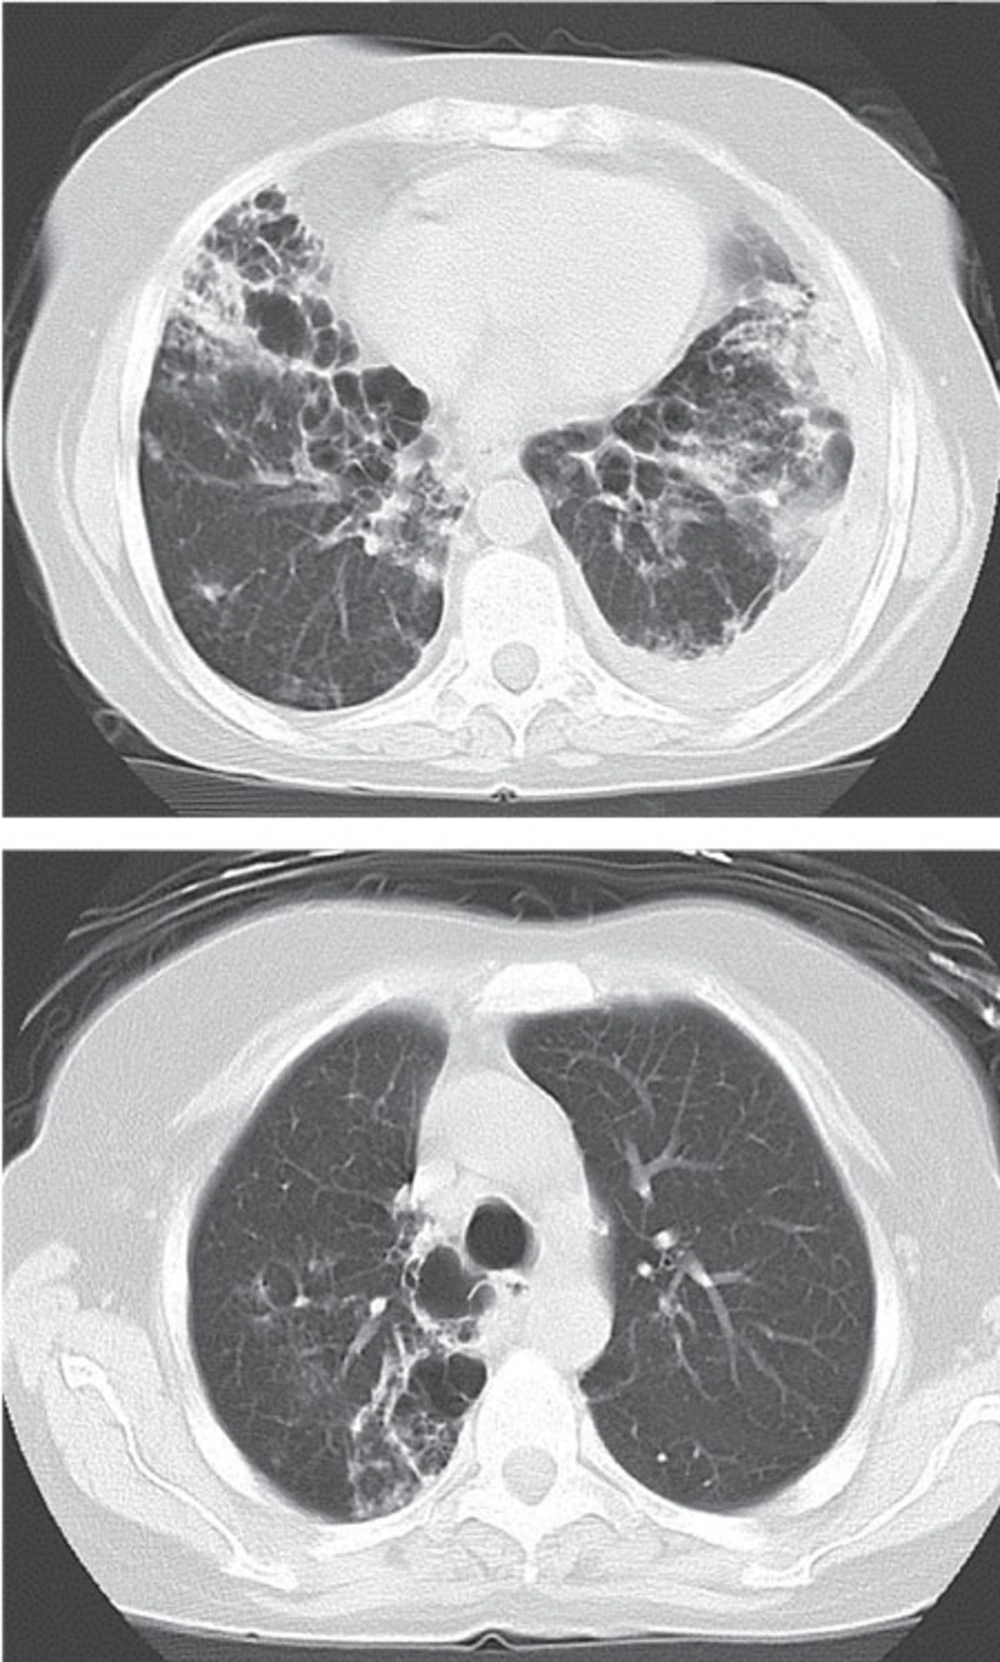

Eventually, a sputum culture revealed a heavy growth of Nocardia. Nocardia was also isolated from a BAL specimen culture after 48 hours. Therefore, piperacillin-tazobactam and azithromycin were discontinued and a combination of amikacin (10 mg/kg in two divided doses) with imipenem (500 mg q6h) was administered. On subsequent visits, she had made remarkable improvements. A normal brain CT scan excluded brain involvement. Three weeks after taking this antibiotic in combination with prednisolone (5 mg), hydroxychloroquine (once daily) and MTX (once weekly), the antibiotic regimen was changed to trimethoprim/sulfamethoxazole (800 mg q12h) (Figure 2). Interestingly, the polymerase chain reaction (PCR) of the BAL specimen revealed M. tuberculosis, therefore, an anti-tuberculosis regimen (including isoniazid 300 mg/d, rifampin 600 mg/d, pyrazinamide 1 000 mg/d and ethambutol 800 mg/d) was added to her previous medication; at follow-up, the BAL culture also confirmed the presence of M. tuberculosis. Three weeks after discharge, the patient complained of severe right shoulder pain and presented with zoster which was treated with three weeks of oral acyclovir (800 mg 5 times/d).